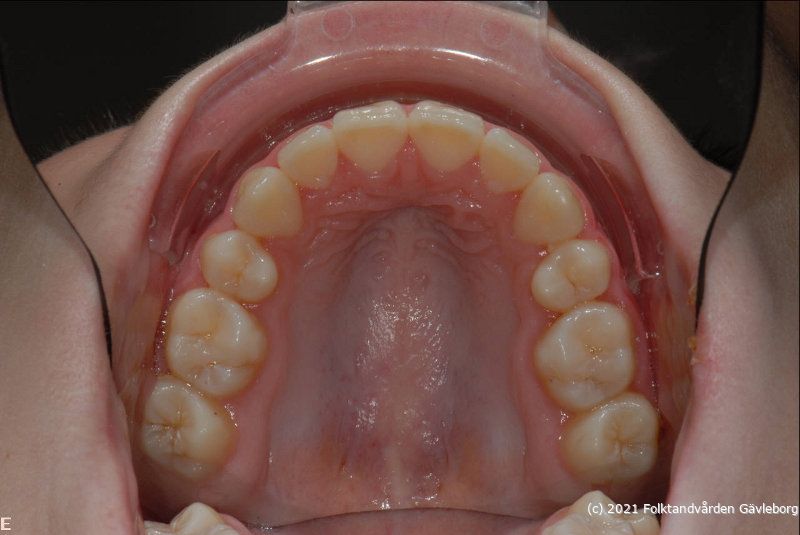

Intraorala bilder med spegel:

• ök    avstånd ca 0,6 m

• uk              -  ”   -

• io04Överkäken

• io05Underkäken

Hjälpmedel: Enkeländad munvinkelhållare samt värmd fotospegel. Ökad blixtexponeringskompensation (+1,0) vid spegelbilder.

Samma inställning mellan ök / uk = samma bildskala! Ovanstånde inställningar och avstånd gäller för 105 mm objektiv.